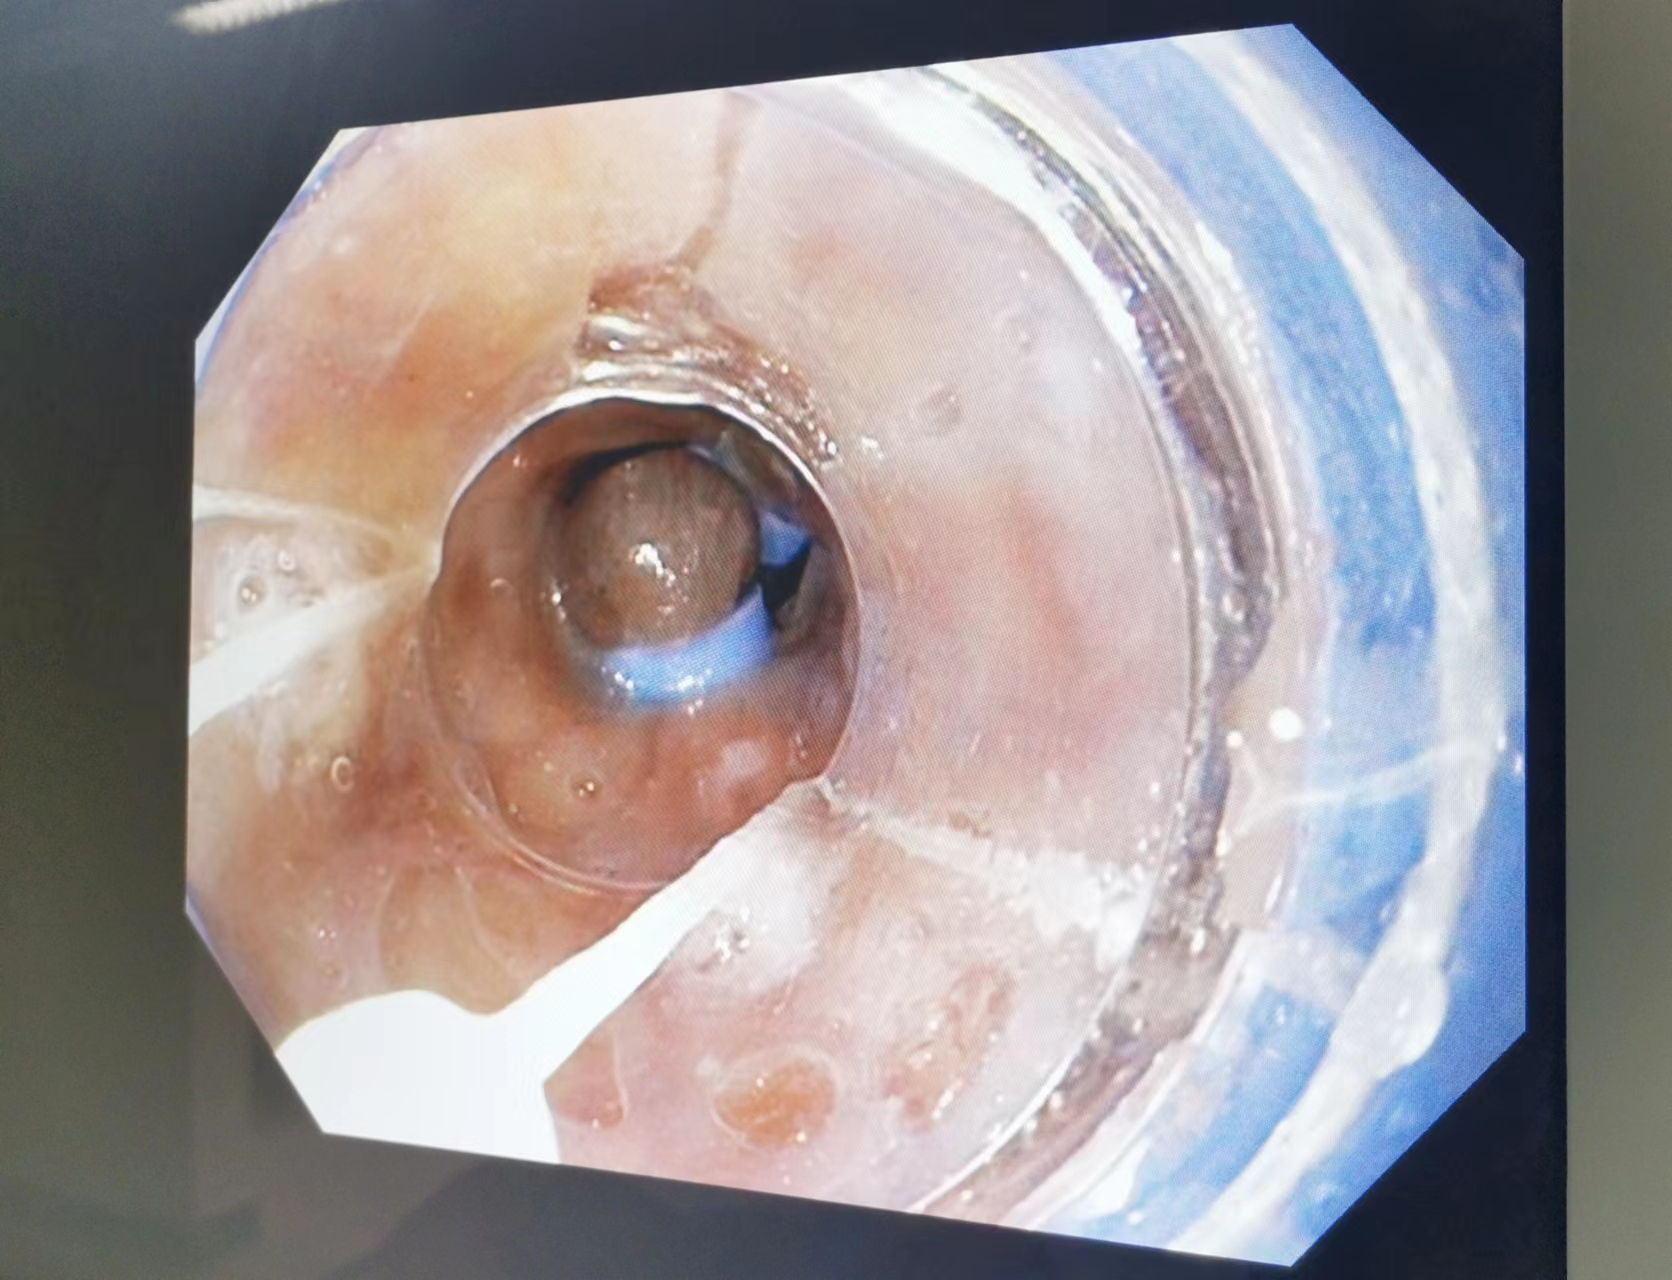

经胃镜食管静脉曲张套扎术

1.常规胃、肠镜检查,内镜下活检术、EMR、息肉切除术、止血术、异物取出术,食道胃底静脉曲张套扎或硬化剂注射止血等多项内镜下微创治疗。